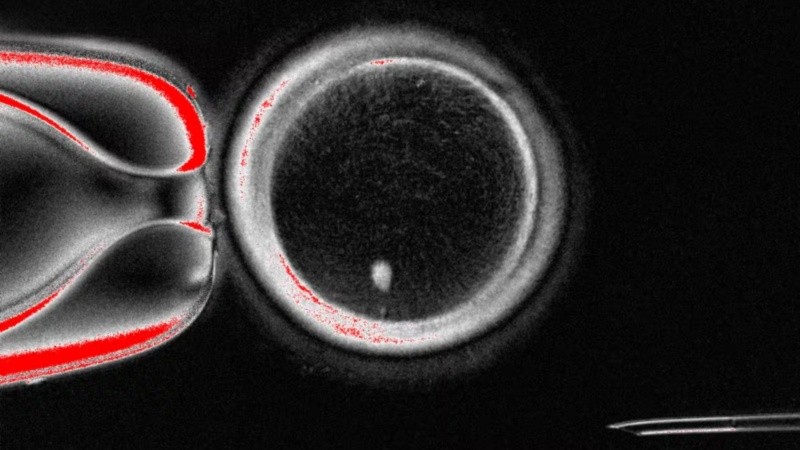

Con este experimento se obtuvieron 82 óvulos funcionales que fueron fecundados con esperma humano. Un 9% alcanzó la fase de blastocito, correspondiente a los primeros seis días de desarrollo embrionario. Si bien ninguno se cultivó más allá de ese punto, para los autores se trata de una prueba de concepto que demuestra la viabilidad de generar gametos humanos por medio de células somáticas.

Como la mayoría de embriones no progresó, a la vez que se detectaron anomalías genéticas, se requieren más estudios antes de plantear posibles aplicaciones clínicas.

“Todavía no hemos conseguido que los 23 cromosomas correctos se eliminen al formar el corpúsculo polar”, explicaron. Y agregaron: “Esto ocurre porque, al introducir el núcleo de una célula somática en el óvulo, los cromosomas homólogos no se alinean correctamente en el nuevo huso acromático. Al no producirse ese emparejamiento, la separación durante la división genera muchas alteraciones genéticas (aneuploidías) que impiden el desarrollo normal del embrión”.